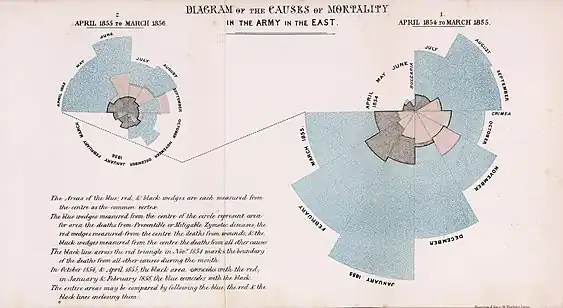

Selected image –

Photo credit: Public domain (U.S. Brookhaven National Laboratory)